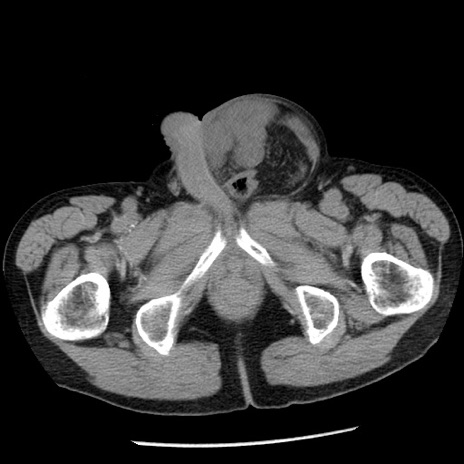

症例26(横断像)

【症例】80歳代男性

【主訴】嘔吐

【現病歴】昨晩2回嘔吐あり、今朝になっても嘔吐あり。来院。

【既往歴】胃潰瘍

【身体所見】意識清明、BT 37.6℃、BP 166/95mmHg、HR 100bpm、SpO2 97%、腹部:平坦・軟、腸蠕動音聴取良好、圧痛なし。

【データ】WBC 21900、CRP 1.46